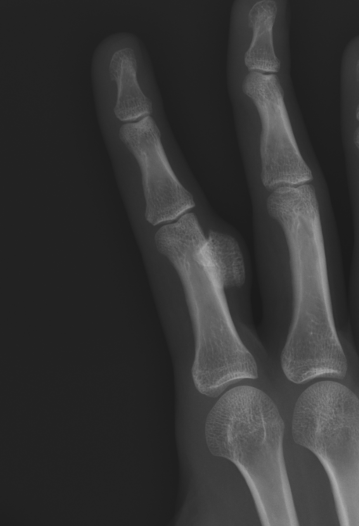

Most common in the hands followed by the feet

- 59% hands

X-ray

Well defined bony mass arising from the surface of the bone

- no medulla